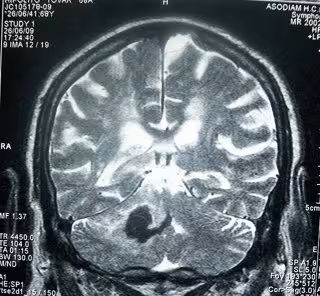

Ictus, Cerebro, Infarto Cerebral

BOBJGALINDO/WIKIMEDIA COMMONS